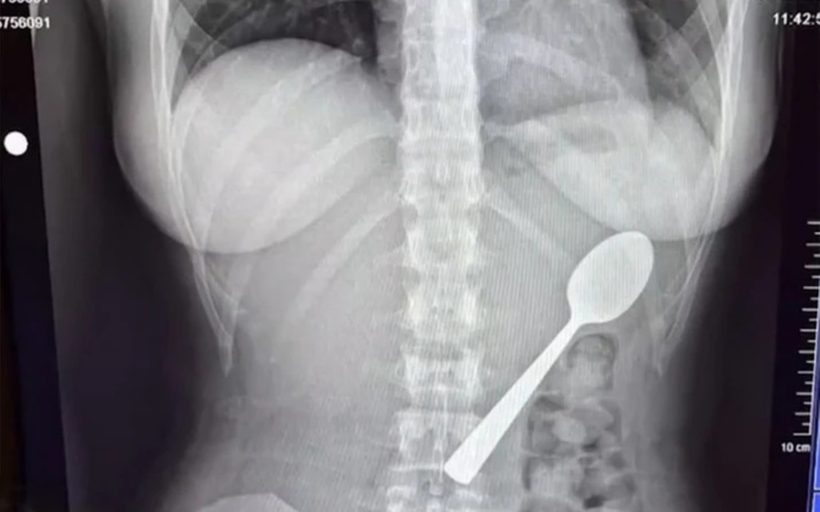

Γυναίκα κατάπιε κουτάλι 17 εκατοστών

Αναυδοι έμειναν οι γιατροί βλέποντα την ακτινογραφία μιας γυναίκας στο Βέλγιο, καθώς διαπίστωσαν πως στο σώμα της βρισκόταν ένα κουτάλι!

Η 28χρονη κατάπιε το κουτάλι 17 εκατοστών, το οποίο κόλλησε στο στήθος της, όταν ενώ έτρωγε στον καναπέ του σπιτιού της, της «όρμησε» το σκυλάκι της.